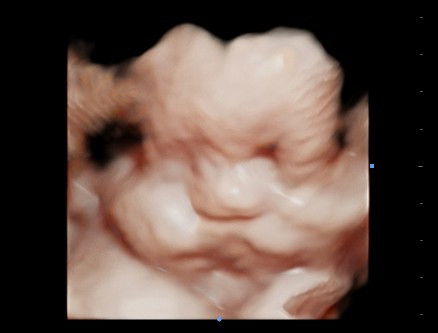

Flek cokelat di kehamilan 8w2d

Halo Bun , aku mau share .. kemarin malam pulang beraktivitas aku liat di CD ada flek cokelat , tanpa disertai gejala lain.. aku langsung panik banget , dan langsung kedokter , kata dokter ancaman keguguran 50%:50% 🥲 diliat saja maksimal sampai 2minggu kedepan , tapi kalo flek makin banyak harus segera kedokter lagi.. sedih walau ini anak ke3ku .. padahal dari awal kehamilan aku minum penguat kandungan dan vitamin , nanti siang rencananya aku mau ke dokter lain buat liat second opinion.. mudah²an mendapatkan kabar yang lebih baik.. mohon doa ya bun semuanyaa .. dan adakah bunda² yang pernah mengalami flek cokelat , tapi kehamilan ttp berlanjut dan sehat sampai lahiran ?#seriusnanya #ingintahu